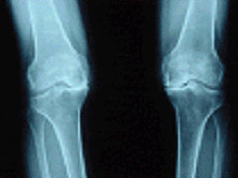

나이가 들어가면서 관절이 닳아 없어지는 퇴행성관절염은 특히 무릎 관절에 많아 인공관절 치환술을 받게 되는 가장 흔한 원인입니다. 휴식과 물리치료, 약물요법 등에 효과가 없고 염증 및 통증이 심할 경우 통증을 없애고 관절의 운동 및 안정성을 회복시키는 목적으로 시행합니다.

류마티스성 관절염이 악화되면 심한 관절 파괴 및 변형을 초래하면서 통증이 조절되지 않습니다. 이런 경우에도 인공관절 대치술을 받아야 합니다. 부위별로 보면 무릎 관절의 류마티스성 관절염으로 인공관절 치환술을 받는 경우가 가장 많고 엉덩이 관절에도 자주 있으며 손가락 관절을 수술하는 경우도 있습니다.